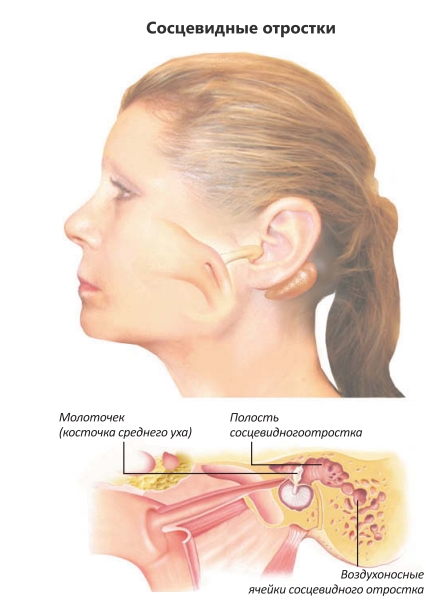

Анатомия сосцевидного отростка